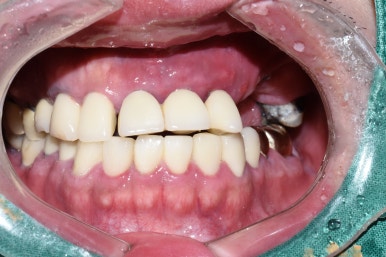

임플란트 수술 전

처음 오셨을 때 기존에 앞니 다른데서 하신 브릿지는

속치아가 다 썩어 분리되어 흔들리는 상태였고

어금니쪽 임플란트는 찢어져서 임플란트 머리를 올리지 못한 상태였습니다.